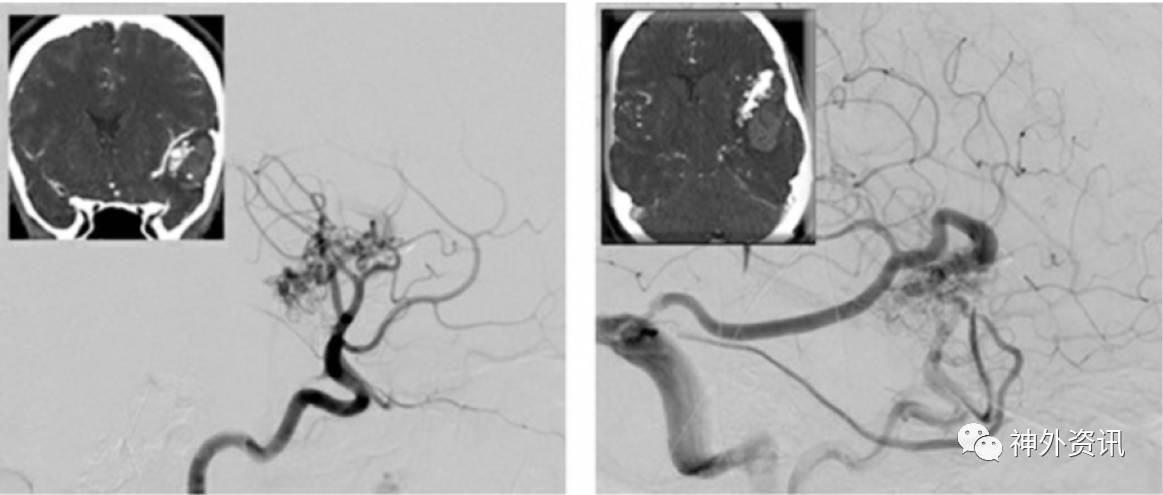

图14. 图示另一个颞叶后内侧AVMs。大多数供血动脉源自P2分支(上图)。血肿腔为经皮层入路显微外科操作提供了宽敞的空间。过度增生的P2穿支血管被切断(中图)。移除AVMs (下图)。